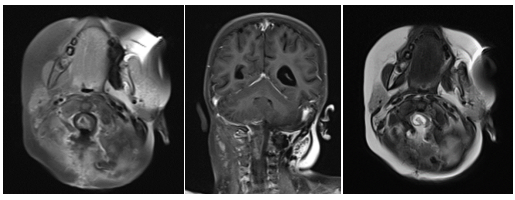

术后影像

术后MRI

然而术后恢复之路仍充满波折。因并发脑积水,患儿出现呕吐等症状,经脱水治疗效果不佳。医疗团队与家属充分沟通后,再次为阿什利施行脑室-腹腔分流术,术后脑积水显著改善。与此同时,医院为她制定并实施了系统化疗方案,历经5个周期的药物调整与精心治疗,至今年7月MRI复查显示术区强化灶已完全消失。